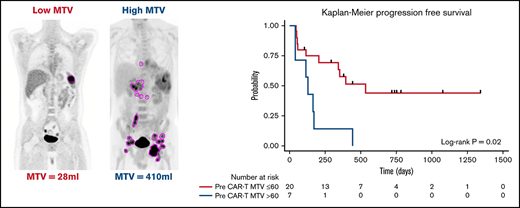

MTV measurement

All patients had baseline 18F-FDG PET/CT scans before lymphodepletion and CD30.CAR-T cell infusion. In patients who had a 18F-FDG PET/CT prior to bridging therapy, these scans were evaluated for MTV to provide a tumor burden comparison before and after bridging therapy. 18F-FDG PET/CT scans were evaluated using MIM 7.0.5 (MIM Software, Cleveland, OH). MTV was computed using the threshold tool in MIM with a threshold 41% of the maximum standardized uptake value (SUV), or SUVmax, as described elsewhere.10-14 The lesion was manually selected and the region of interest increased until all voxels at least 41% of the SUVmax (Figure 1). MTV for each patient was determined by summing the volumes of lesions with voxels at least 41% of the SUVmax.

The median time from 18F-FDG PET/CT scan to CD30.CAR-T cell infusion was 12 days (range, 4-35 days). MTV calculated from 18F-FDG PET/CT scans obtained after bridging therapy (if applicable) and before lymphodepletion and CD30.CAR-T cell infusion were evaluated by a twofold, cross-validating analysis. This revealed a trend toward inferior PFS in patients with high pre–CAR-T MTV (P = .07; Table 2). After adjusting for lymphodepletion, high pre–CAR-T MTV was associated with inferior PFS (P = .03). Analyzing pre–CAR-T MTV with a cutoff of 60 mL revealed that high MTV > 60 mL was associated with inferior PFS in both the unadjusted model and after adjustments for lymphodepletion and CAR-T dose (P = .02, 0.01, and 0.006, respectively; Figure 3A). The 1-year PFS estimate was 14% (95% CI: 1%-46%) and 58% (95% CI: 33%-76%) in the high and low baseline MTV groups, respectively.